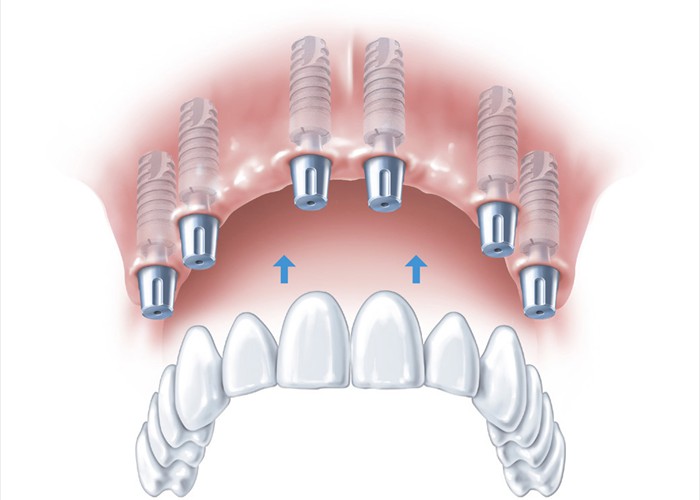

Das Einsetzen des fertigen Zahnersatzes

Das Einsetzen des fertigen Zahnersatzes

Die eingesetzte Versorgung - ästhetisch und funktionell perfekt

Die eingesetzte Versorgung - ästhetisch und funktionell perfekt